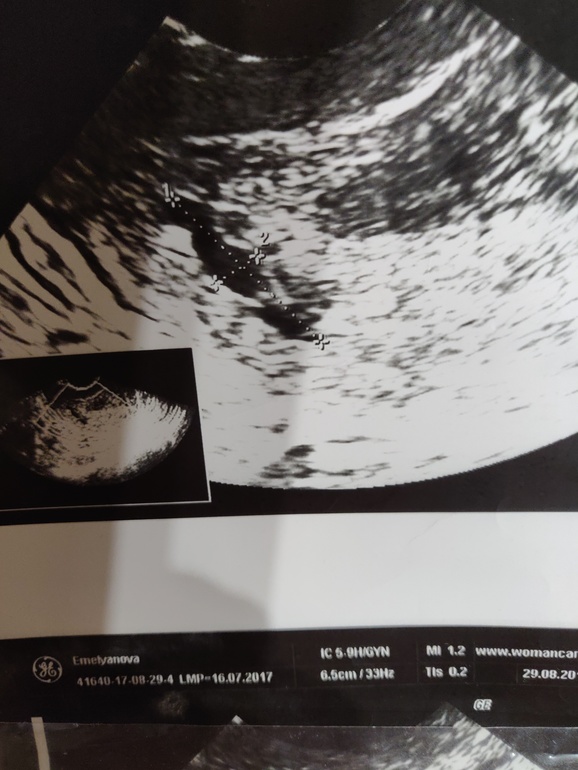

УЗИ 5 недель.

Вопросы про УЗИ, обследования и анализы: что, где, как, когда?Здравствуйте, девочки! Сегодня ходила на первое УЗИ, убедиться что всё хорошо. Доктор сказал что всё ему нравится, всё по сроку, только увидел в матке 3 анэхогенных включения. Говорит что на гематому не похоже, надо наблюдать в динамике. Может у кого было такое на ранних сроках, чем закончилось? Буду благодарна за ответы!

Гематомы выглядят на узи иначе, действительно не похоже. Если бы я увидела первое фото без вашего описания то я бы честно говоря подумала что на нем тройня сроком недель 5. Но я так понимаю это исключено...

Гематома между плодными яйцами:

Как правило они не круглые